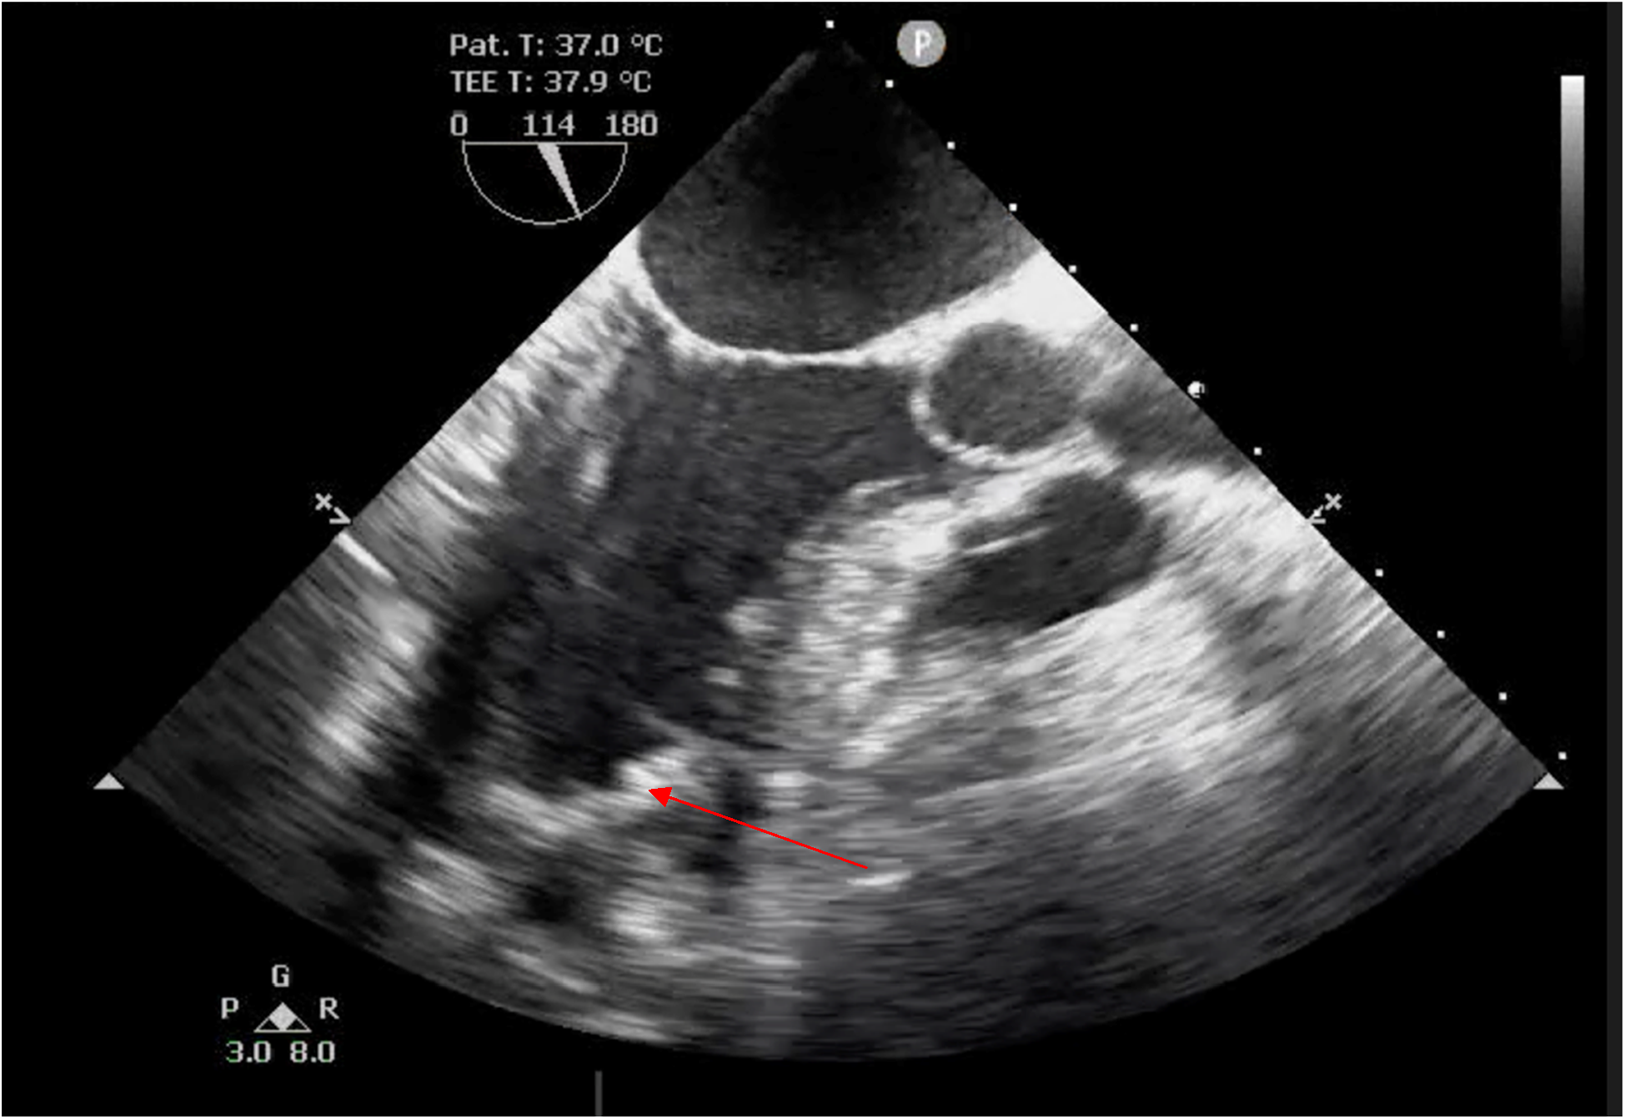

The duration of CPB was 36 min. The time of artificial lung ventilation was 11 h. There was no need for cardiotonic agents. The next day after the surgery, the patient was transferred to the general ward from the intensive care unit, and verticalization of the patient was attempted. He was discharged in stable condition on the fifth day. Basic EchoCG data at discharge were as follows: left ventricular end-systolic volume, LV EDV = 135.3 ml (EDV index—67.6 ml/m2), LV ESV = 62.0 ml (ESV index—31 ml/m2); LVEF = 54.2%. TEE after the surgery shows physiologically more correctly formed LV geometry (Figure 4).

Figure 4

TEE after the surgery. LV, systole. The arrow points at the patch.